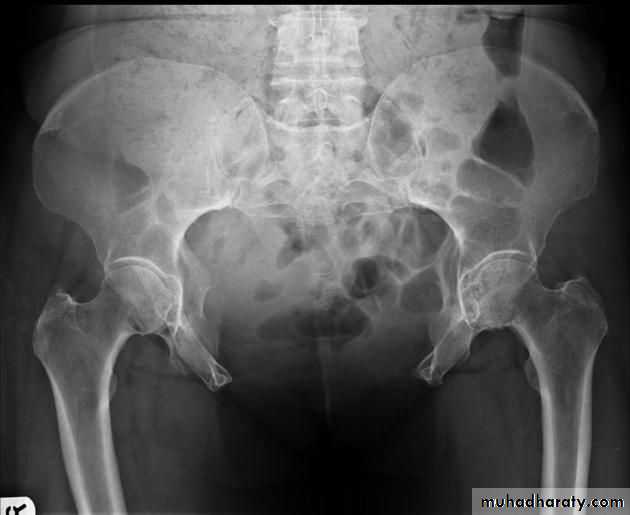

radiographic appearance in bladder exstrophy. It describes wide midline separation of the pubic bones.Bladder exstrophy (also known as ectopia vesicae) refers to a herniation of the urinary bladder through an anterior abdominal wall defect. The severity of these defects is widely variable.